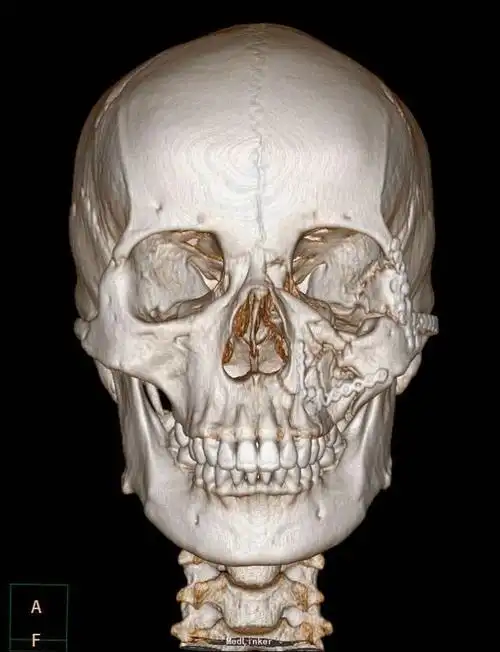

【急诊】颧骨骨折,上颌骨骨折ct表现